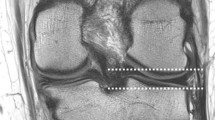

After processing, the 2D MR Images and the 3D models were reviewed by three residents in orthopedic surgery (Res), three senior orthopedic surgeons (OS), and two fellowship trained Musculoskeletal (MSK) radiologists. The residents in orthopedic surgery were all in their fifth year of their 6 year residency program. The orthopedic surgeons had an average experience of 11 years (2, 7 and 25 years) in ACL reconstructive surgery. The MSK radiologists had an average experience of 5 years in reading MRI scans of the knee (both 5 years). None of the observers had any previous experience at identifying the femoral footprint on MRI. Observers were invited separately at the 3D laboratory of our institute. Each observer was asked to identify the center of the femoral footprint of the ACL of all 20 cases. Observers had access to the anonymized MRI and the 3D model of the femur in Mimics, an example of the screen the observers were exposed to is shown in Fig. 1. The observers could switch between a high resolution MRI image of either the sagittal, axial or coronal plane.

Using the Mimics software, observers were asked to place a circle of 8 pixels in diameter on a sagittal MRI image of their choice, with the other planes and 3D model as a reference, at the center of the patient specific femoral footprint of the ACL. An example is shown in Fig 2. After approximately 1 week the procedure was repeated by the same observers. All observers were blinded to the results of their first session and those of the other observers. As the observers were not trained in Mimics, a medical student trained in Mimics was present at both sessions for practical questions and to ensure smooth logistics.